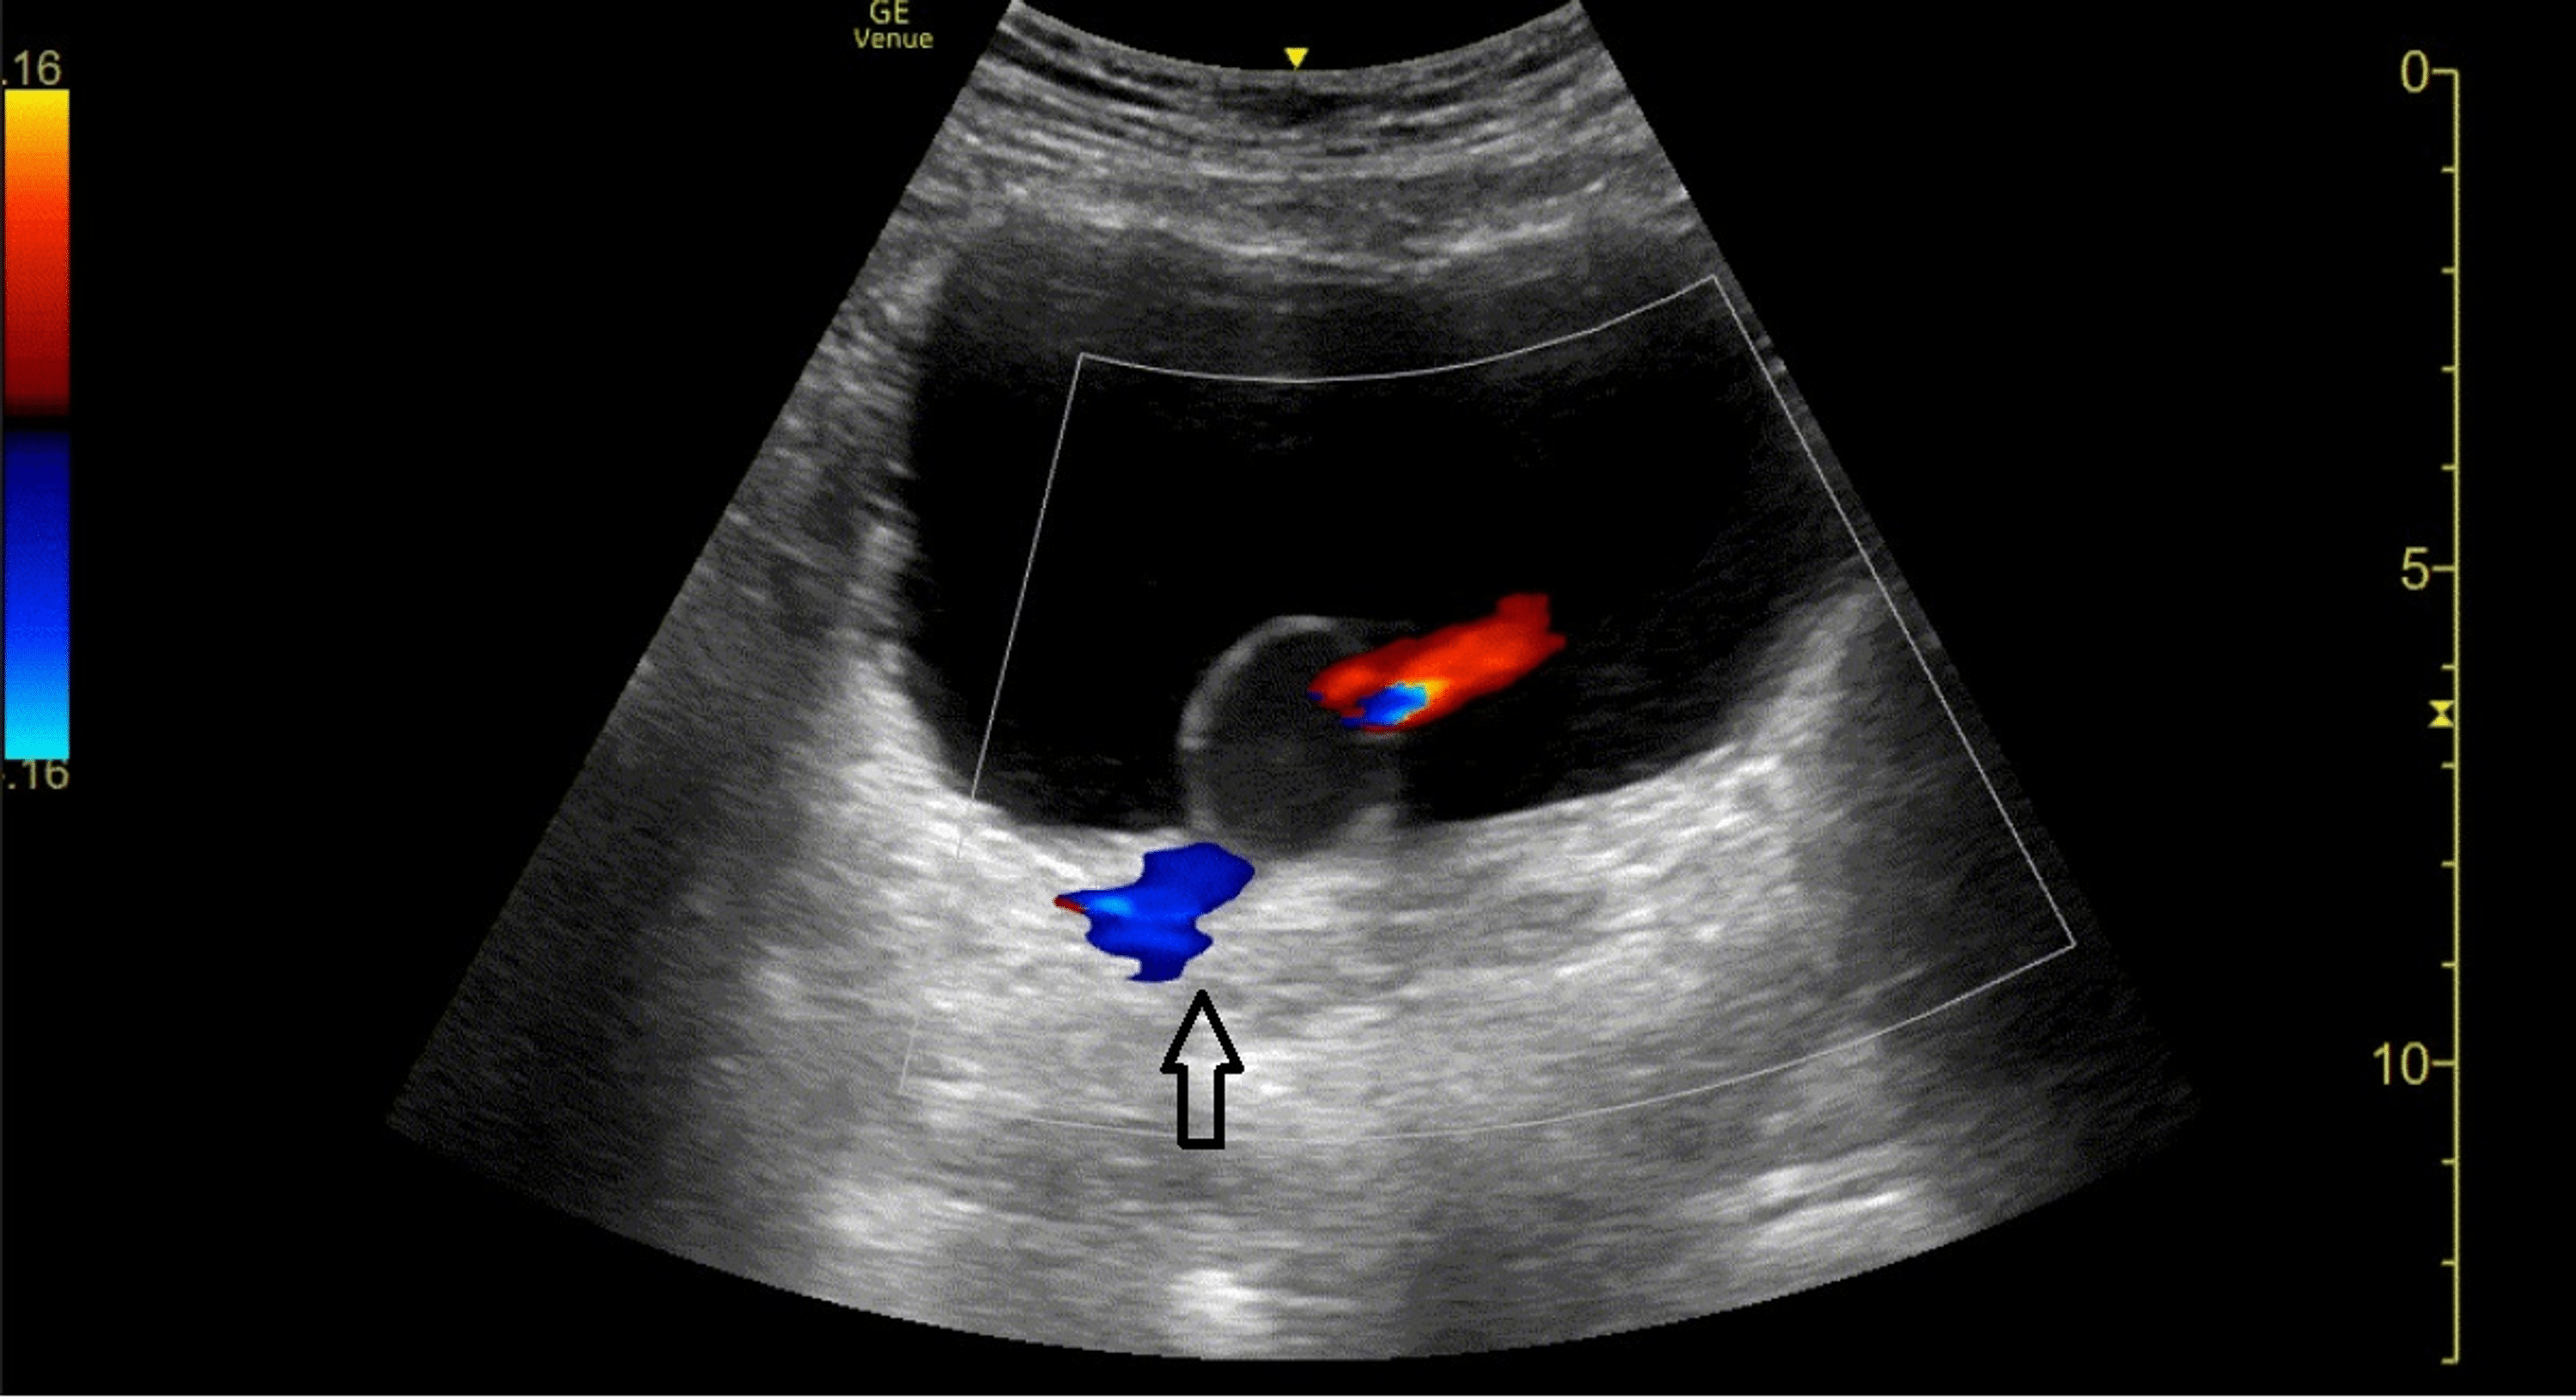

From www.cureus.com

Cureus Ureterocele Diagnosed With PointofCare Ultrasound Endoscopic Decompression Ureterocele While numerous studies of endoscopic management. endoscopic decompression is usually definitive for single system intravesical ureteroceles [8, 9]. — it may be noted as an incidental finding on antenatal ultrasonography, or it may be identified. — multiple punctures at the basis of the ureterocele, performed by low laser energy, is resulted a really minimally. — urgent. Endoscopic Decompression Ureterocele.